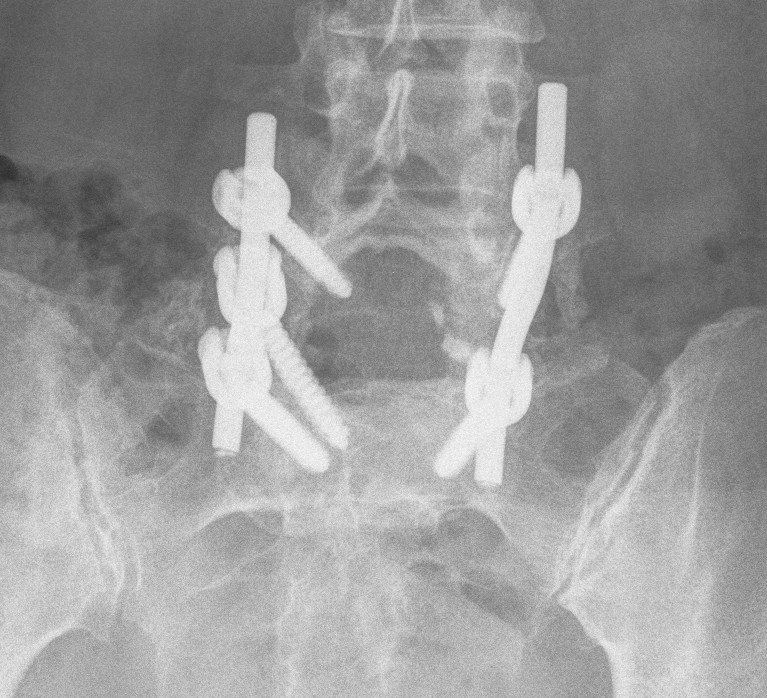

Instrumented fusion in situ without reduction

Indications

- slip grade 1 or II

- grade III or IV with no sagittal malalignment

Levels instrumentation

- L5 / S1 grade I or II

- L4 / S1 grade III or IV

Options

1. Pedicle screw instrumentation

2. PLIF / interbody cage

3. Bohlman procedure

- interbody fusion with fibula strut

- augmented with decompression and PLF

4. Transfixing L5 / sacral screw